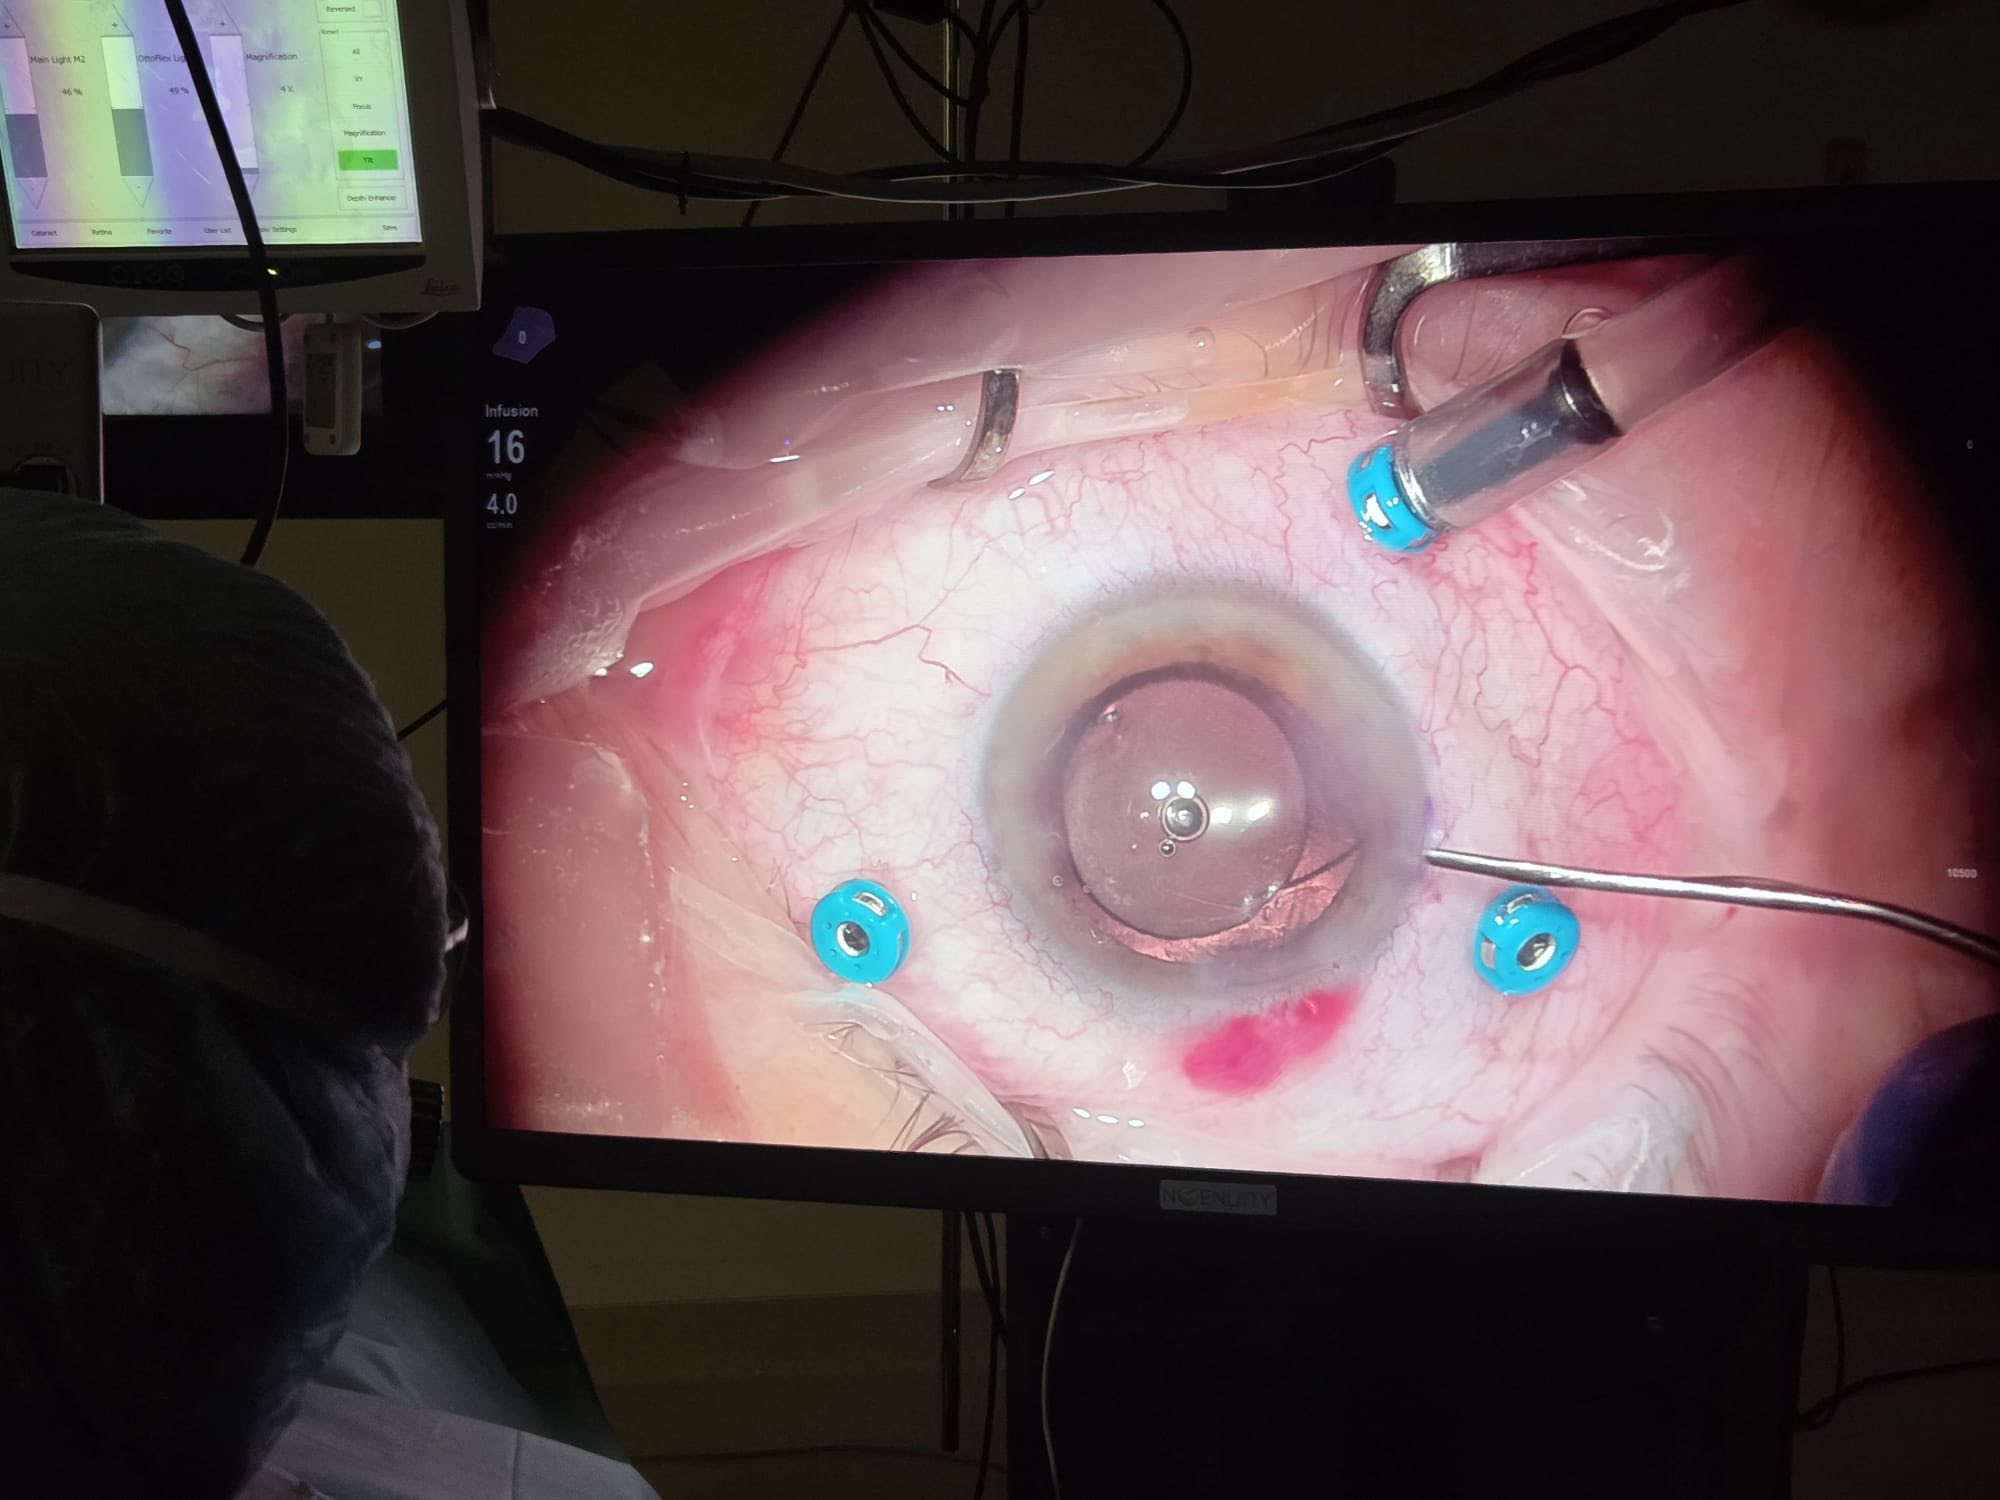

Intervenția, efectuată de dr. Ozana Moraru, a fost vitrectomie prin pars-plana, decolarea membranelor fibroase de la suprafața retinei, aplicații endo-laser în jurul dializei retiniene și circular, pe 360 de grade, decolarea membranei ILM din aria maculară și tamponadă cu ulei siliconic.